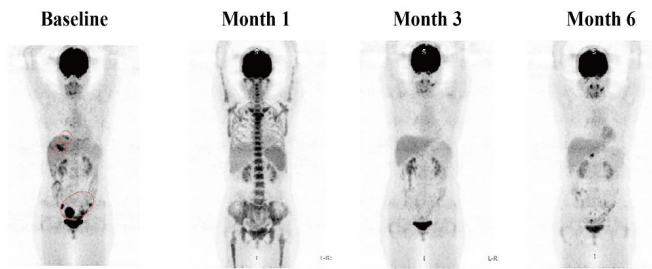

Significant reduction in abdominal and pelvic target lesions, achieving partial remission

Three months post-treatment, the volume of liver metastases significantly reduced, and the liver lesions showed no FDG uptake, achieving partial remissionLatest research results presented at the 2025 Gastrointestinal Cancer Symposium showed that researchers evaluated two different doses of GCC19CAR-T. In dose group 1 (1 x 10⁶ cells/kg), 4 evaluable patients were included, with an overall response rate (ORR) of 25.0%, where 1 patient achieved confirmed partial remission (PR), and 2 patients showed partial metabolic remission with stable disease (SD); while the performance in dose group 2 (2 x 10⁶ cells/kg) was even more impressive, with an ORR of 80.0% among 5 patients, where one fortunate patient had all tumor target lesions disappear, achieving pathological complete remission! Three lesions significantly reduced, achieving partial remission, and another patient showed complete metabolic remission in PET/CT examination. Overall, across both dose levels (9 patients in total), the ORR reached 56%. The disease control rate was 75% in dose group 1 and 80% in dose group 2, with an overall disease control rate of 78%.